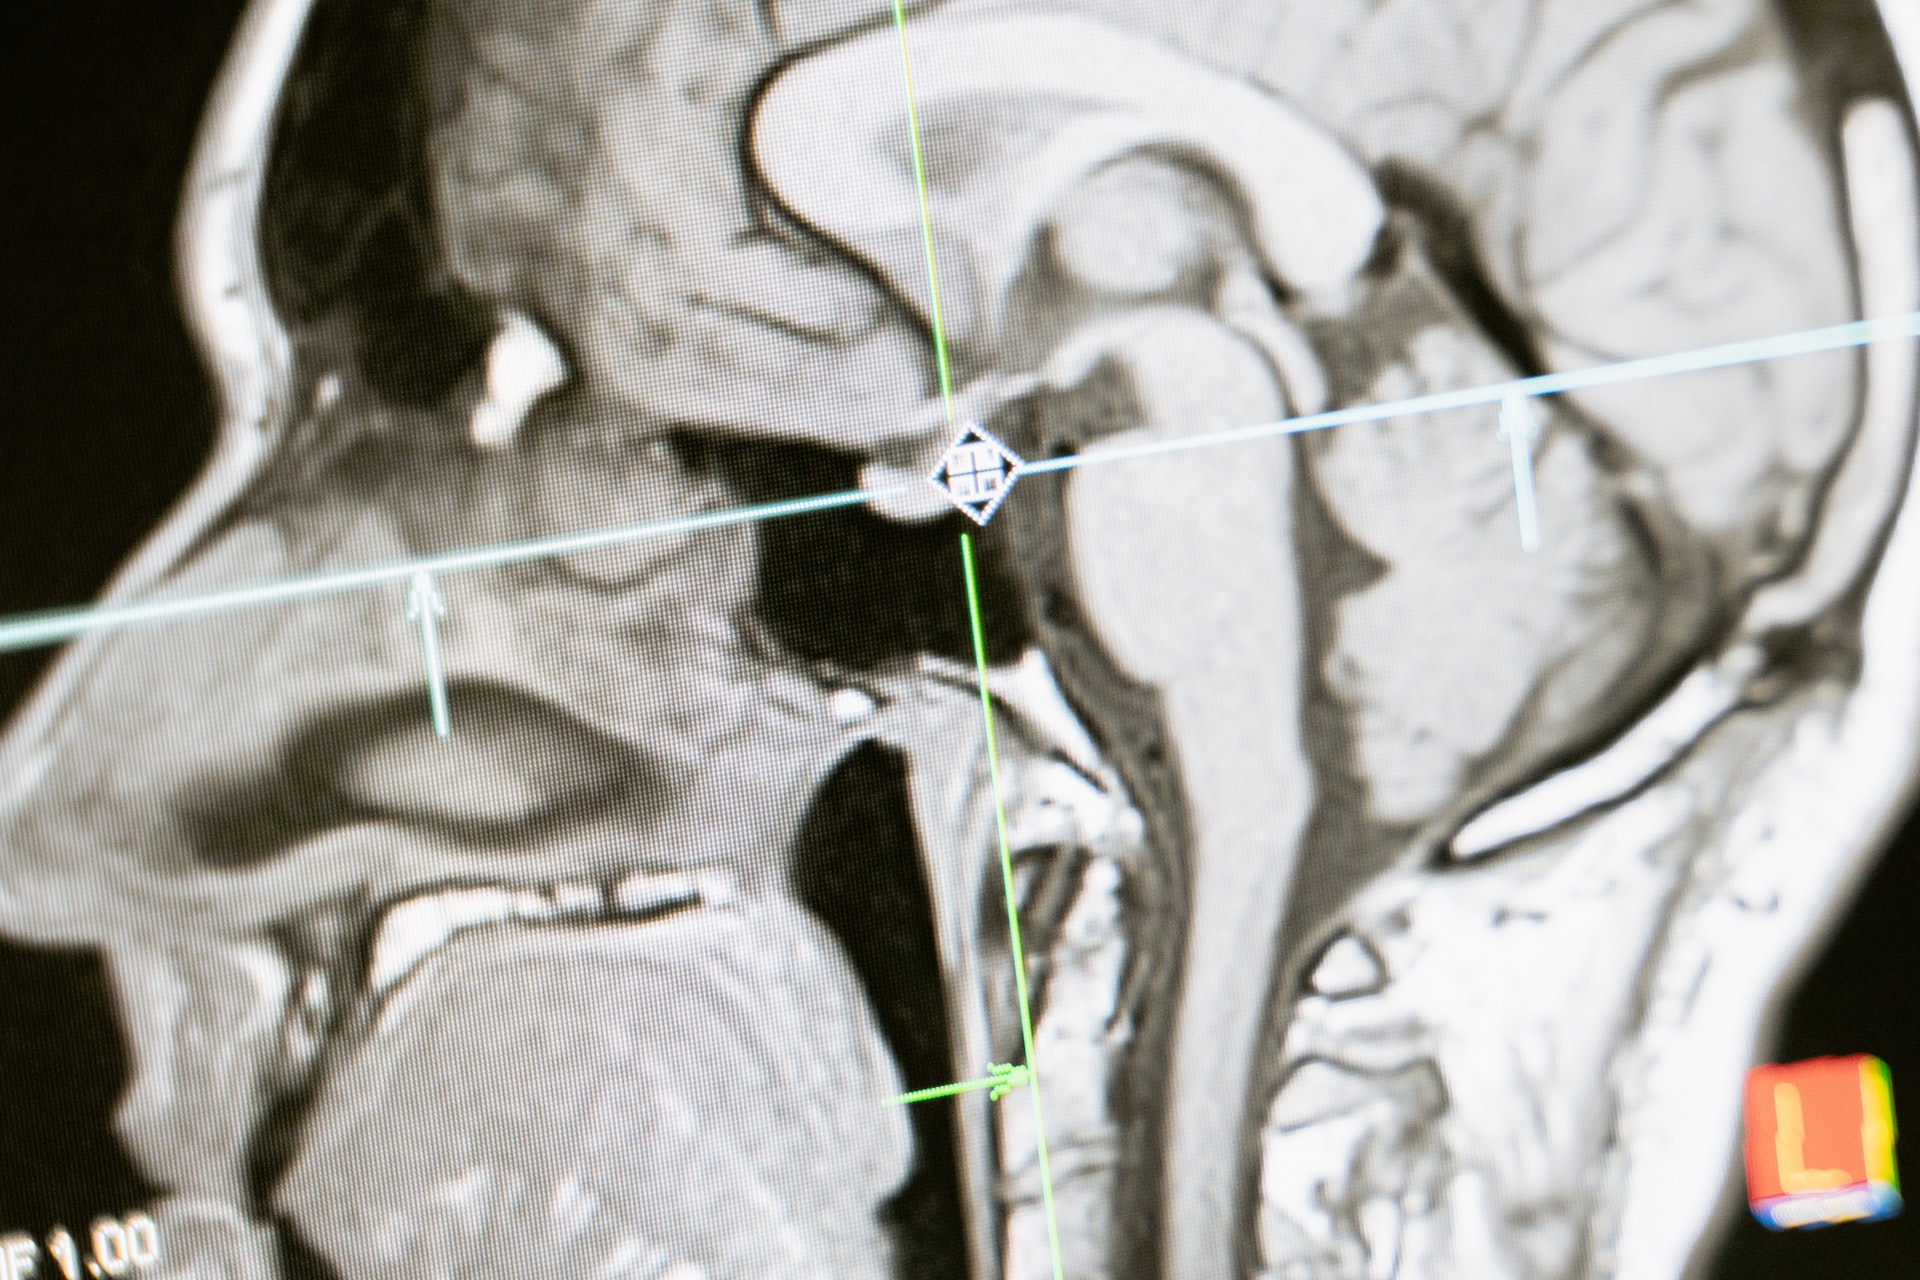

Modelele de învățare profundă bazate pe inteligența artificială (AI) pot identifica rasa umană pe baza radiografiilor, au dezvăluit noi cercetări, ceva ce ar fi imposibil pentru un medic care privește aceleași imagini.

Descoperirile ridică câteva întrebări îngrijorătoare cu privire la rolul AI în diagnosticul, evaluarea și tratamentul medical: ar putea prejudecățile rasiale să fie aplicate neintenționat de către un software de calculator atunci când se studiază imagini ca acestea?

După ce au antrenat un AI folosind sute de mii de radiografii etichetate cu detalii despre rasa pacientului, o echipă internațională de cercetători în domeniul sănătății din SUA, Canada și Taiwan a testat sistemul pe radiografii pe care pe care computerul nu le mai…